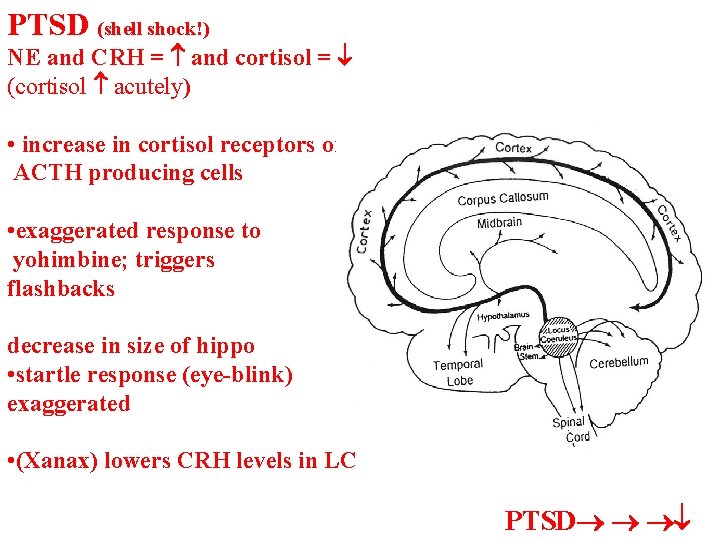

PTSD (shell shock!) NE and CRH = and cortisol = (cortisol acutely) • increase in cortisol receptors on ACTH producing cells • exaggerated response to yohimbine; triggers flashbacks decrease in size of hippo • startle response (eye-blink) exaggerated • (Xanax) lowers CRH levels in LC PTSD

PTSD (shell shock!) • horror of a battle is US • sights, sounds smells are conditioned by amygdala • CS can then turn on amygdala unconsciously and turn on long term memories about original event or recent episodes when trauma was relived low frequency r. TMS (repetitive • patient listens to tape of transcranial magnetic stimulation) traumatic experience MRI leads to a decrease in regional activity in amygdala and limbic cerebral blood flow cortex (especially on right side) shocking data